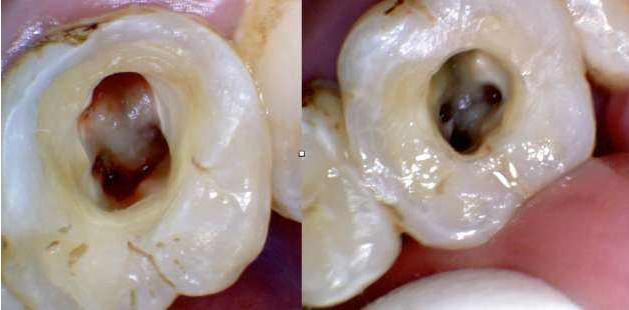

这是因为如果牙齿需要根管治疗的话,一般已经是没有完整的牙冠了的,且牙体表面并不是整齐的缺损,是有一定的尖锐棱角的。

而根管治疗后,牙体髓腔内部的物质已经被部分或者是全部清除了,这样牙体是处于一个中空状态的,所以牙齿会相对来说比较脆弱一些,那么如果患者咀嚼较硬的食物的话,就很容易对剩余的牙体造成伤害,出现劈裂或者是崩断的状况。

1,根管治疗是需要开髓的,那么牙体上部分是被清除的,在形态上牙齿就会少一部分,做牙冠会在很大限度上恢复牙齿的外观形态及使用功能。

2,根管治疗是需要在清理掉感染物质后填充药物到髓腔内部的,如果一直处于开髓后的牙体状态的话,对于后期的恢复不利,也会更容易使细菌进入到患牙深层内部。

3,开髓后的牙齿失去了牙体本来的硬组织保护,而牙髓内部的物质被清除后,牙体会变得脆弱,很容易受到外力而发生断裂。剩余牙体也容易因为失去牙髓而缺少营养补给,变得灰暗脆弱,牙冠就可以在很大程度上保护剩余的牙体不受到二次伤害。